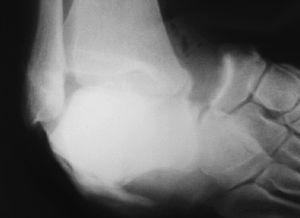

El seguimiento a la largo plazo de las fracturas del astrágalo identifica que la causa más común de los resultados pobres está asociada con la OA subastragalina, tibioastragalina y talonavicular, tanto en nuestra revisión, que alcanzó al 21% (8) de los casos (figs. 9 y 10), como en otros trabajos revisados15,17,19,22,23.

Fig. 9. --A) Fractura del cuerpo del astrágalo tipo B más rotura completa de los 3 ligamentos laterales del tobillo. B) Abordaje bilateral. Osteosíntesis. Sutura de ligamentos. Radiografía y tomografía computarizada a los 18 meses. Artrosis subastragalina y tibioastragalina.

Fig. 9. --a: Type B fracture of the astragalus with complete rupture of the 3 lateral ankle ligaments. b: Bilateral approach. Osteosynthesis. Ligament suture. Radiography and CT at 18 months. Sub-astragalar and tibio-astragalar arthrosis.

Fig.10. --Resultado a los 32 meses. 50° de BA. NAV del cuerpo y artrosis subastragalina y tibioastragalina

Fig.10. --Results at 32 months. BA 50º. Avascular necrosis of the astragalus and sub-astragalar and tibio-astragalar arthrosis.